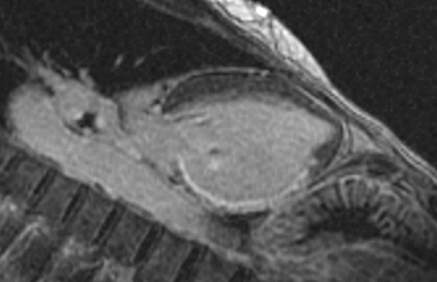

Fig.: 6., 7., 8.: MRI: Extended myocardial infarct of the inferior ventricular wall Late phase contrast enhancement in the thin inferior wall of the ventricle in cross sectional and longitudinal images, MRI